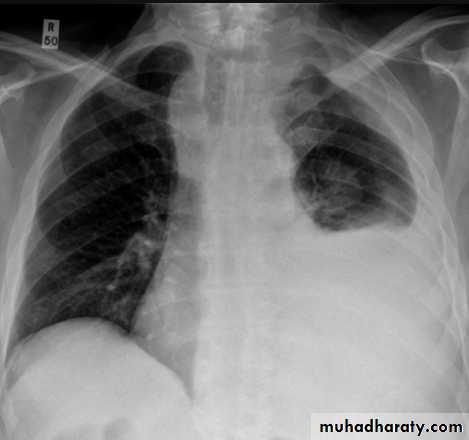

with large volume effusions, mediastinal shift occurs away from the effusion (note: if coexistent collapse dominates then mediastinal shift may occur towards the effusion)

An empyema can resemble a pleural effusion and can mimic a peripheral pulmonary abscess, although a number of features usually enable distinction between the two Features that help distinguish a pleural effusion from an empyema include:

Shape and location

Empyemas usually:

form an obtuse angle with the chest wall

unilateral or markedly asymmetric whereas pleural effusions are (if of any significant size) usually bilateral and similar in size .

lenticular in shape (bi-convex), whereas pleural effusions are crescentic in shape (i.e concave towards the lung)

Empyema